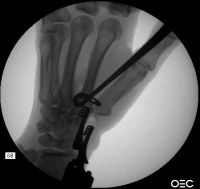

| In this case, a vena cava

ligature passer was modified to create the path around the index

metacarpal base. |